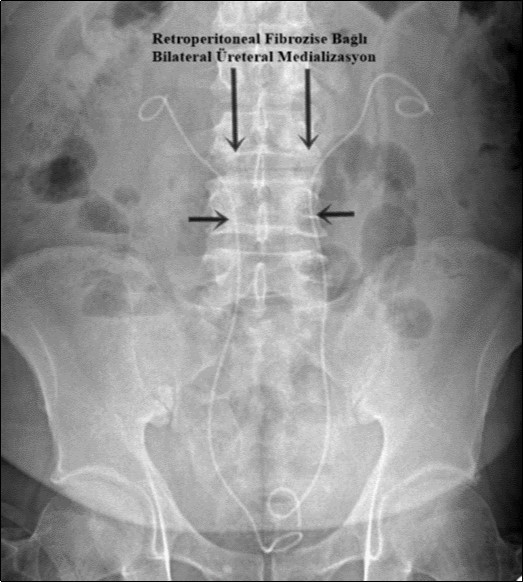

A 58-year-old male patient was admitted to our clinic with complaints of severe weakness, loss of appetite and decreased urine volume. The patient had chronic, mild lower urinary tract symptoms. Serum creatinine level of the patient was 5.3 mg/dl and he had no additional diseases except hypertension. Bilateral grade 3 hydronephrosis and moderate residual urine was revealed in urinary ultrasonography. A transurethral foley catheter was inserted and the patient was admitted to the internal medicine intensive care unit with the diagnosis of acute renal failure due to infravesical obstruction. During follow-up, abdominal magnetic resonance imaging (MRI) was performed due to oliguria and high serum creatinine level (Figure 1). Magnetic resonance imaging revealed a mass of approximately 88x49 mm in the axial plane at the renal artery outlet level, consistent with retroperitoneal fibrosis, tuberculous lymphadenitis or lymphoma. Grade 3 pelvicaliectasis was seen in bilateral kidneys. The descripted lesion was observed in paraaortic area (except posterior). Tru-cut biopsy was planned with no evidence of malignancy on positron emission tomography. Tru-cut biopsy reported as connective tissue. Bilateral double-J ureteral stent was placed endoscopically to patient who was diagnosed as idiopathic retroperitoneal fibrosis (Figure 2). At the same time, alpha-blocker treatment was started. Creatinine levels decreased to normal after five days and normal volume voiding was observed after removal of foley catheter. The patient was started on glucocorticoid therapy which was foreseen to last for 1 year. After 2 months, PET imaging showed the decreased mass size and metabolic activity. Thereafter bilateral ureteral double-J stents were removed endoscopically. Ultrasonographic imaging showed no hydronephrosis after 7 days of catheter removal and the patient was recommended to continue glucocorticoid therapy and was followed up.

Figure 2.Ureteral diversion with bilateral double-J catheter. Both ureters were pulled medially due to retroperitoneal fibrosis.

Ureteral diversion with bilateral double-J catheter. Both ureters were pulled medially due to retroperitoneal fibrosis.